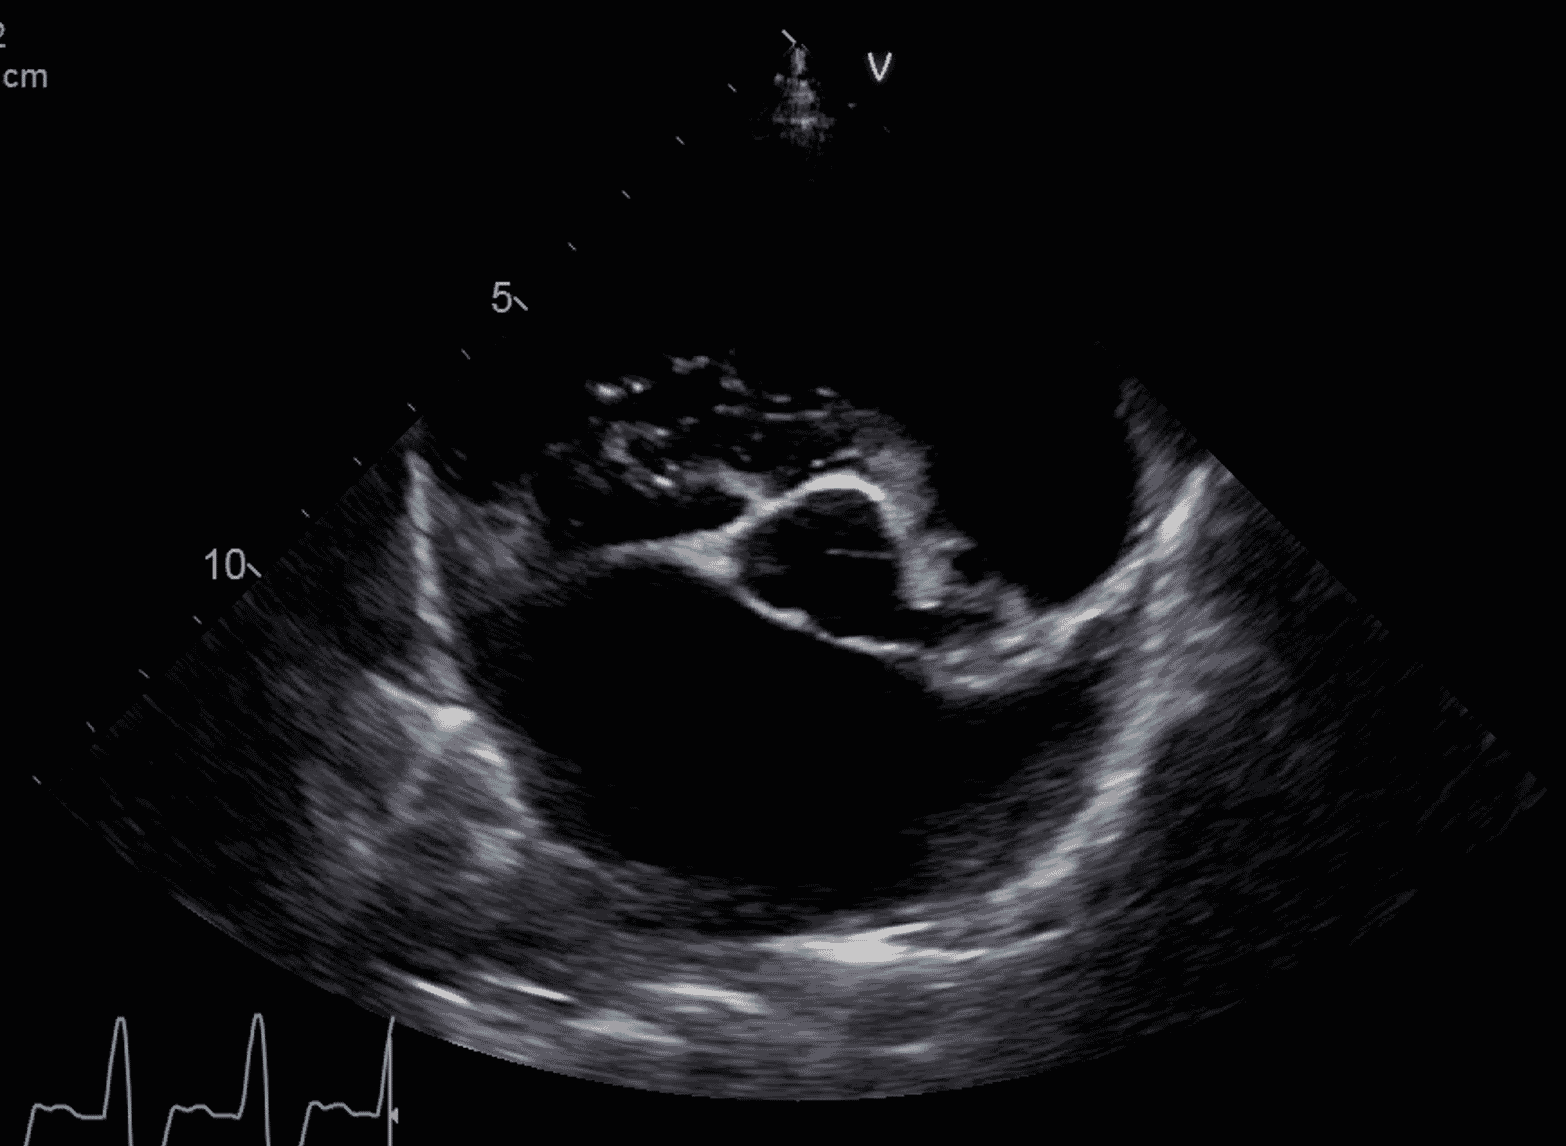

Here, we will be focusing on acute left-sided heart failure, caused by mitral valve disease (MVD) or dilated cardiomyopathy (DCM) ( Figures 1 and 2). In dogs, these make up probably 95 percent of the cases of heart failure identified in primary care practice, with the remaining being caused by arrhythmogenic right ventricular cardiomyopathy (especially in Boxers and Bulldogs), arrhythmia-induced heart failure (relatively common in working breeds) or congenital heart diseases such as patent ductus arteriosus (almost exclusively puppies of predisposed breeds).

The dog with DCM and persistent pulmonary oedema

Dilated cardiomyopathy causes poor output in combination with pulmonary oedema. Mitral regurgitation may or may not be present, but the most important factor impeding this dog’s recovery is poor systolic function and therefore low cardiac output. Some clinicians express concerns about administering diuretic drugs to patients with hypotension and pulmonary oedema, fearing renal injury or worsening of hypoperfusion. However, increased preload (blood volume) in dogs with severe systolic dysfunction can itself reduce cardiac output. If preload is reduced with furosemide, output should increase (or at least not reduce significantly) in DCM ( Figure 5). Some heart diseases, such as mitral stenosis, are relatively preload dependent, so dogs with this problem (rare outside of the English Bull Terrier) should receive more cautious diuretic doses.